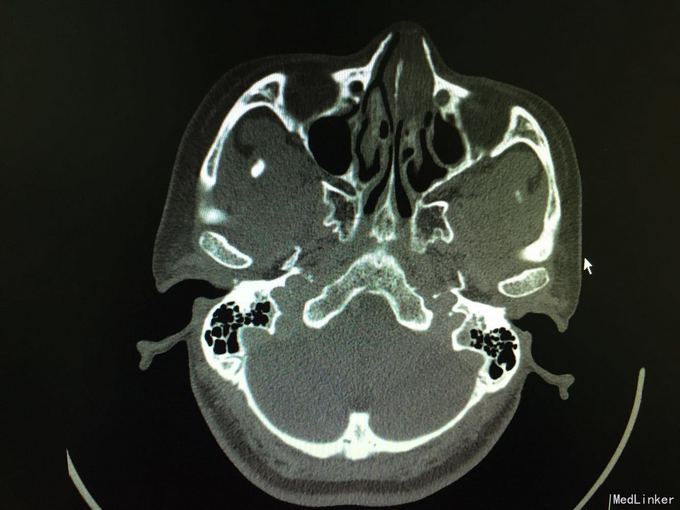

以“间断性左鼻腔出血5月,加重1月”为主诉入院。5月前劳累后出现左鼻腔出血,量中等,可自止,无明显鼻塞、流涕、鼻腔异味,自行口服药物后异味消失(具体药物不详),未正规治疗,1月来左侧鼻腔间断性出血,约3-5天1次,量少,偶浓涕、头晕,无明显鼻痒、喷嚏症状。

查体:双侧鼻腔黏膜充血,左侧总鼻道可见肿物,表面糜烂,质硬,触之易出血,左侧中鼻道窥不及,右侧鼻腔各鼻道未见明显新生物,无活动性出血,鼻中隔偏曲。 增强CT显示肿物内强化明显。

诊断:1.鼻腔血管瘤(左) 2.鼻出血(左) 3.结构性鼻炎 介入手术后3天行低温等离子左鼻腔肿瘤切除术